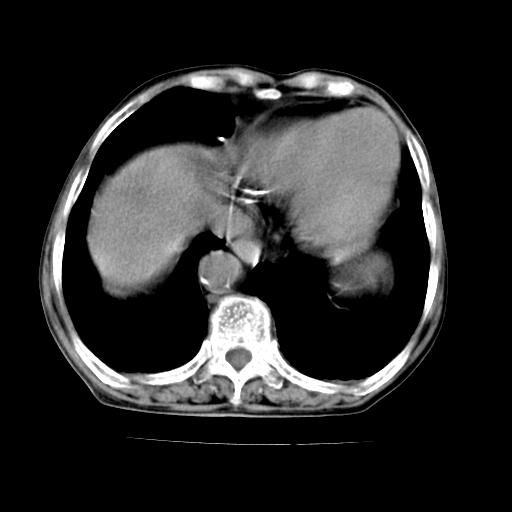

标题: CT19149:女,68岁,腹胀、恶心两周。 [打印本页]

标题: CT19149:女,68岁,腹胀、恶心两周。

女,68岁,腹胀、恶心两周,先做ct平扫,当时家属不同意强化,6天后家属要求增强扫描。